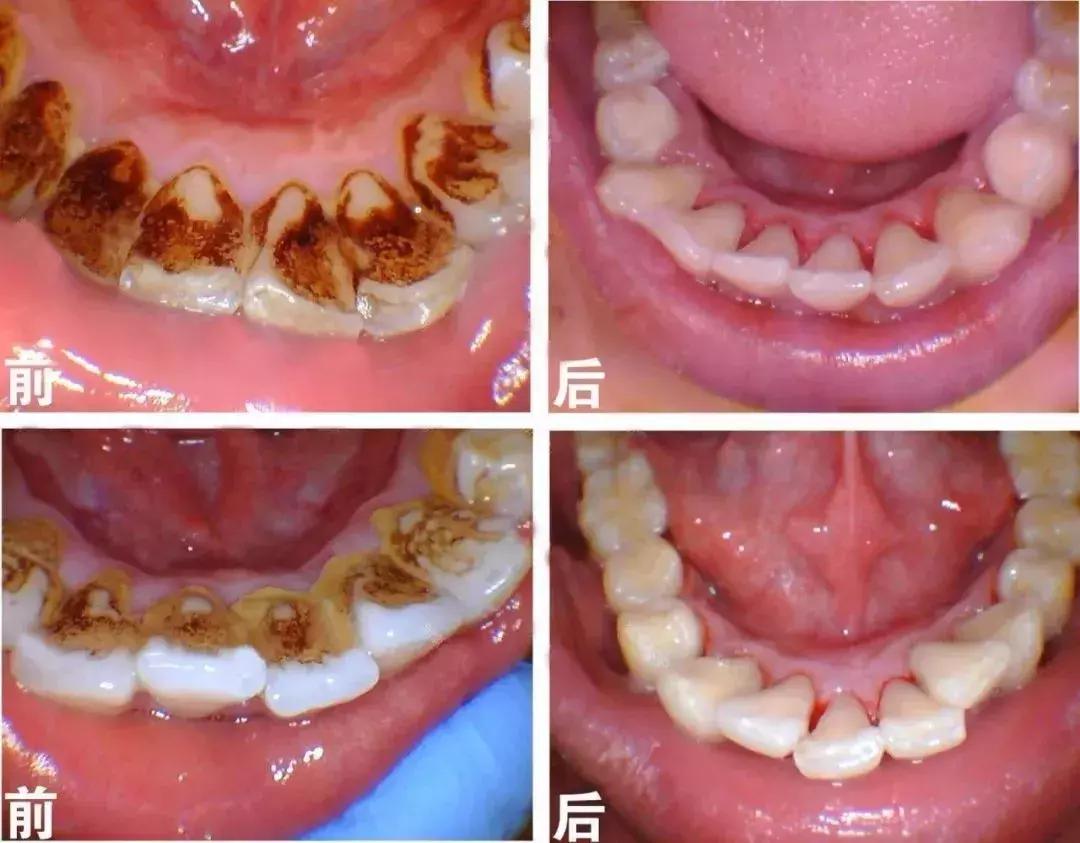

洗牙前后对比图